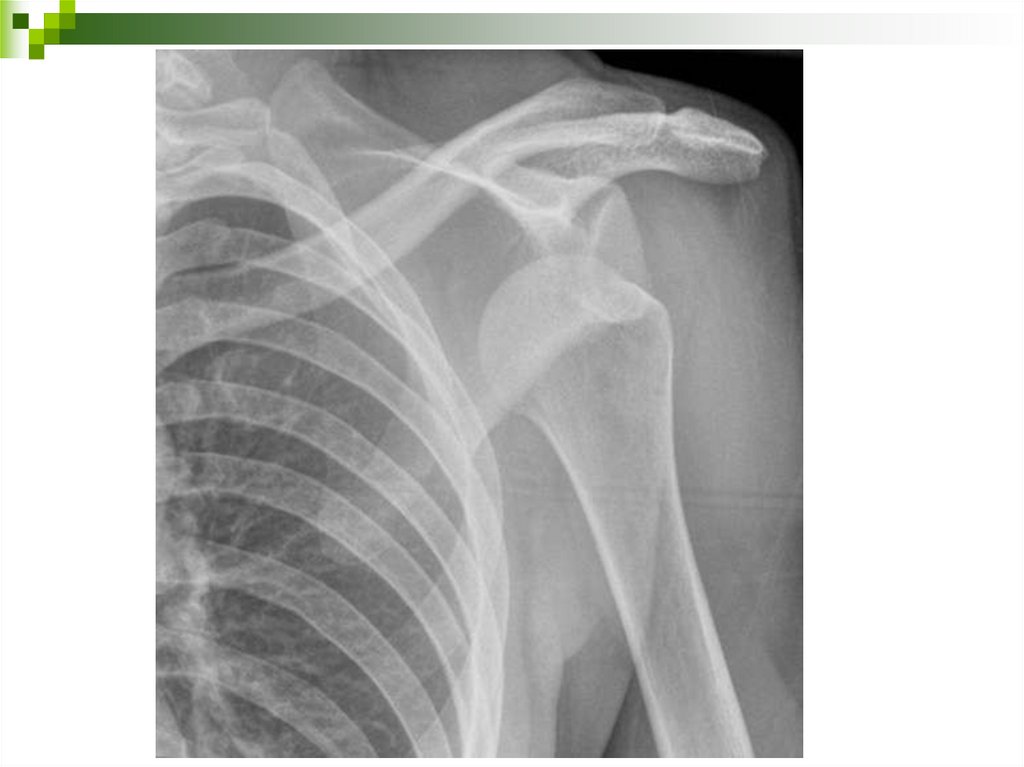

Повреждения плечевого пояса.

Перелом ключицы.

Клиника: боли в ключице резко усиливаются при движении рукой,

глубоком дыхании, кашле. Надплечье выглядит укороченным, под

кожей заметна деформация и определяется подвижность

отломков, позже возникает отек, кровоизлияние. Рука кажется

более длинной, больной прижимает её здоровой рукой к туловищу,

голова наклонена в сторону повреждения.

Доврачебная помощь – согласна алгоритму

Транспортировка в полусидячем положении.